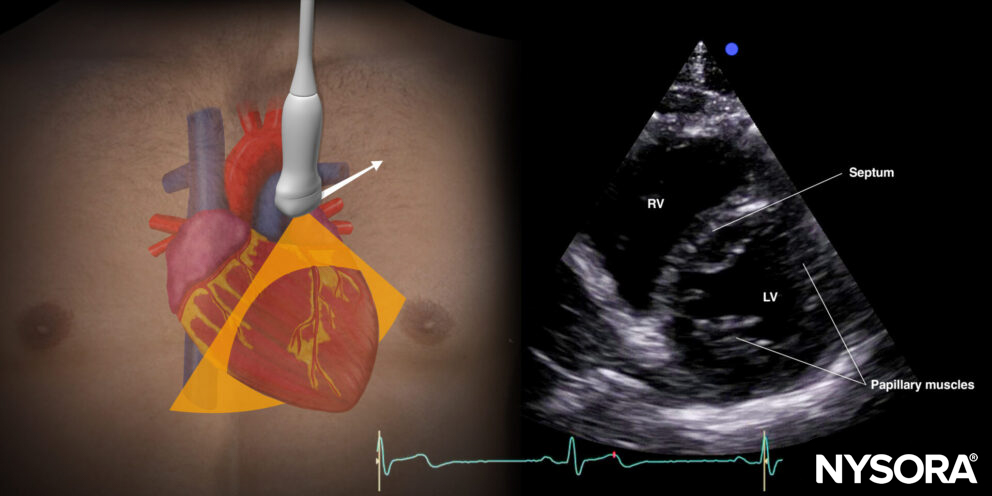

- To rule out right ventricle dilatation, it is best to use the parasternal short-axis view. The right ventricle should have a crescent shape. High right ventricular pressures will cause the septum to bulge into the left ventricle. This is also called left ventricular D-shaping.

Ultrasound and Reverse Ultrasound Anatomy of the parasternal short-axis view